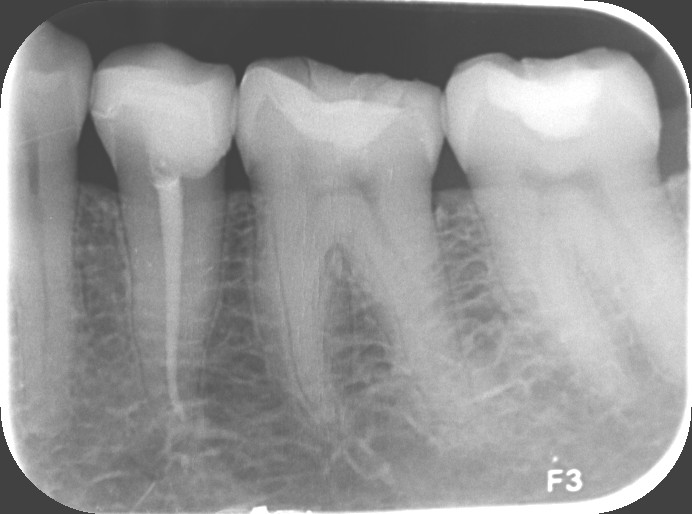

La Dra. Amdie y su equipo de especialistas en endodoncia en Bogotá tienen una misión clara: salvar tus dientes sin dolor y proteger tu sonrisa. Con años de experiencia somos líderes en tratamientos de endodoncia sin molestias. Confía en nosotros para brindarte soluciones personalizadas y efectivas que te permitan mantener tus dientes naturales sanos y funcionales.